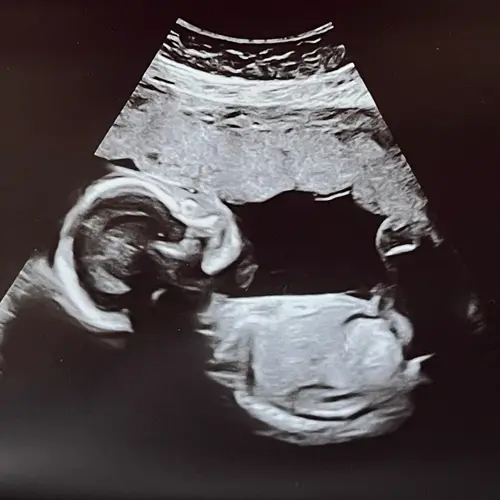

Ik heb vanochtend exact hetzelfde nieuws gekregen! Onze baby heeft ook enigszins korte beentjes en hebben volgende week de GUO. Na mijn Google sessie kwam ik er wel dat als de rest goed is, het vaker het geval is dat er niks aan de hand is.

Oh echt meid. Wat een toeval zo allebei tegelijk! Maar wat spannend ook hè, en in jouw situatie nog wat extra lijkt me door de korte beentjes. Wat zeiden ze er bij jou verder van? Ik had inderdaad ook gegoogled. Vaak laat dit je alleen maar slechter voelen natuurlijk, maar merkte dat het me toch wat rustiger maakte! En helemaal omdat onze verdere echo er voor nu wel heel goed uit zag! Maar het blijft nu wel in je hoofd hè.. 🤨

Onze echoscopiste leek in de eerste instantie niet per se heel bezorgd en zij dat het niet iets hoefde te betekenen. Dat het vooral uit voorzorg was! Maar ze had verder geen implicaties of oorzaken genoemd; alleen dus dat hij die witte darmen wat had en dus die korte benen. En bij jou?

Onze gynaecoloog vond t vervelend om te zeggen omdat het “vaak niks is uiteindelijk “ maar ze moest het wel zeggen. En ze twijfelde dus, omdat het minimaal is, ze liet ons ook zien of we het wit of grijzig vonden.. dus het bleef toch een beetje twijfelachtig allemaal. Dat scheelt voor mij wel iets, of dat het echt iets duidelijks is.. 😉

Oh ja was dit topic eventjes vergeten! Hartstikke goed eigenlijk. Gynaecoloog zag geen reden om verder te onderzoeken, want het leek niet ernstig genoeg. We gaan nu gewoon uit van een gezond en enigszins klein kindje!

Hier ook vandaag te horen gekregen dat de darmpjes wat wit kleurden op de echo, was tijdens 20-weken echo/GUO. De NIPT was goed en verder op de echo geen andere aanwijzingen voor iets afwijkends. De gynaecoloog maakt zich op basis hiervan ook niet direct zorgen, maar het blijft inderdaad wel door je hoofd spoken. Ik heb wel direct bloed laten prikken op infecties en een onderzoek aangevraagd naar dragerschap voor CF bij ons. Hopen dat we gewoon bij de >80% horen waarbij het gewoon weer verdwijnt! 🙌🏻🍀